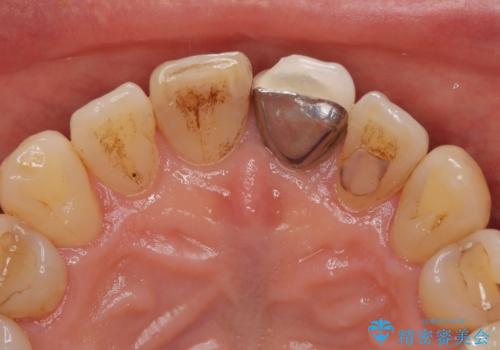

- 幼少期にぶつけてしまった前歯2本の変色を気にして来院された患者様です。

神経は生きているものの歯の色が茶色くなってきており、隣の歯は保険診療で装着したプラスチックのクラウンが徐々に黄ばんできている状態でした。

2本を同時にオールセラミッククラウンにて補綴治療を行うこととしました。